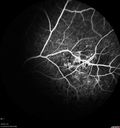

FLUORESCEIN ANGIOGRAPHY: Fluorescein angiography in the right eye shows leakage from the area of retinal infiltrate. In the left eye there is hypo and hyper auto fluorescence corresponding to the leopard spots.